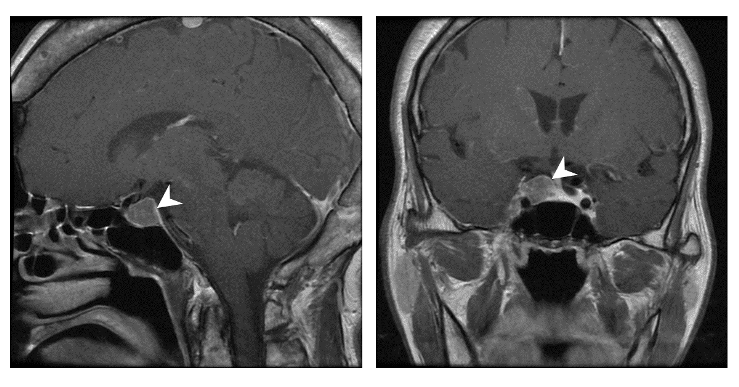

做核磁共振檢查腦下垂體

接下來就是腦部的核磁共振檢查,看腦下垂體是否真的有腺瘤。

結果腦下垂體有一顆已經 2 公分大的腺瘤。